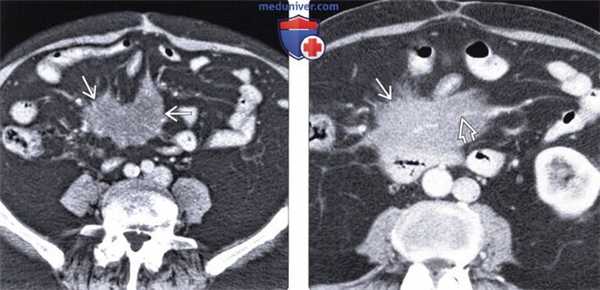

(Слева) На аксиальной КТ с контрастным усилением определяется объемное образование брыжейки инфильтративного характера, вовлекающее брыжеечные сосуды. Обратите внимание на застойные изменения брыжеечных вен. Все это признаки склерозирующего мезентерита.

(Справа) На аксиальной КТ с контрастом у пожилой женщины с болевой симптоматикой и диареей определяется мягкотканное объемное образование в основании брыжейки тонкой кишки, окружающее и сдавливающее брыжеечные сосуды. После биопсии был подтвержден диагноз фиброзирующего мезентерита.